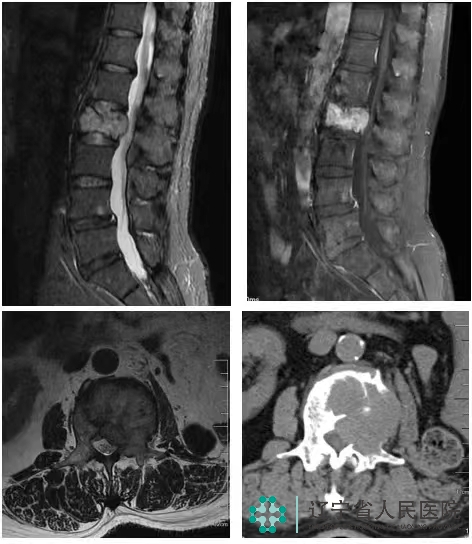

近日,我院骨五科收治了一位来自辽西地区的腰椎转移瘤(肾癌原发)患者。由于患者入院时,腰背痛伴随左下肢麻木疼痛,经腰椎增强MRI等影像学检查后,发现腰2椎体破坏严重,左侧椎弓根已被严重侵蚀,随时可能因病理性骨折,进一步压迫硬膜、导致瘫痪的可能。完善PET/CT后,未发现其他部位的肿瘤转移。

术前